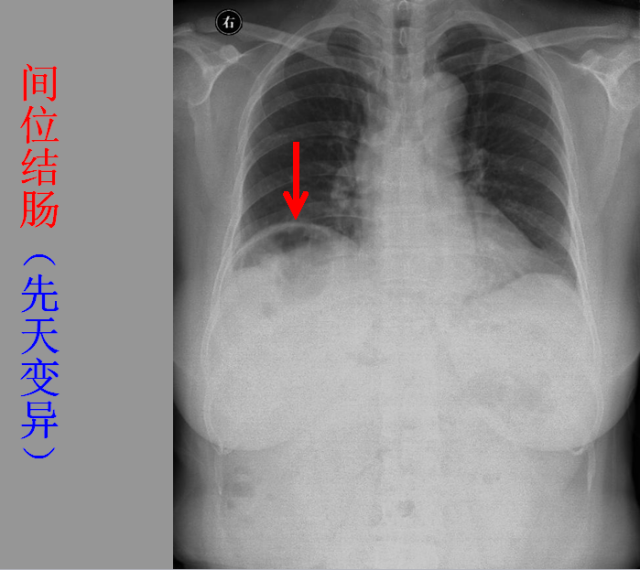

急胸症篇

04